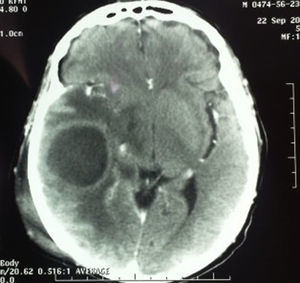

Caso 4Paciente masculino de 52 años con antecedente de enfermedad renal crónica manejado con diálisis peritoneal, referido al servicio con otorrea derecha de un mes de evolución y aumento de volumen en región retroauricular ipsilateral, secundario a traumatismo 7 días previos. En la TC se encontró edema en tejidos blandos en región temporal, una otomastoiditis y un absceso cerebral en lóbulo temporal (fig. 4). El paciente fue tratado mediante craniectomía descompresiva, capsulectomía, drenaje del absceso parenquimatoso, mastoidectomía con muro bajo y drenaje del absceso retroauricular (fig. 5).

Paciente de sexo masculino de 42 años, diabético, referido para valoración por presentar 3 cuadros de meningitis en el último mes. En la TC se observó una mastoiditis derecha. La punción lumbar reportó un líquido cefalorraquídeo turbio, con 6,000leucocitos/mm3 con 65% de polimorfonucleares, 332mg/dl de proteínas, 107mg/dl de glucosa, con un cultivo negativo; glucosa sérica de 279 mg/dl, leucocitos periféricos de 10,100μL (neutrófilos totales del 73%); reacción en cadena de la polimerasa para tuberculosis negativo. Fue tratado con antibioticoterapia a base de vancomicina y meropenem intravenosa por 14 días y mastoidectomía simple (fig. 6).